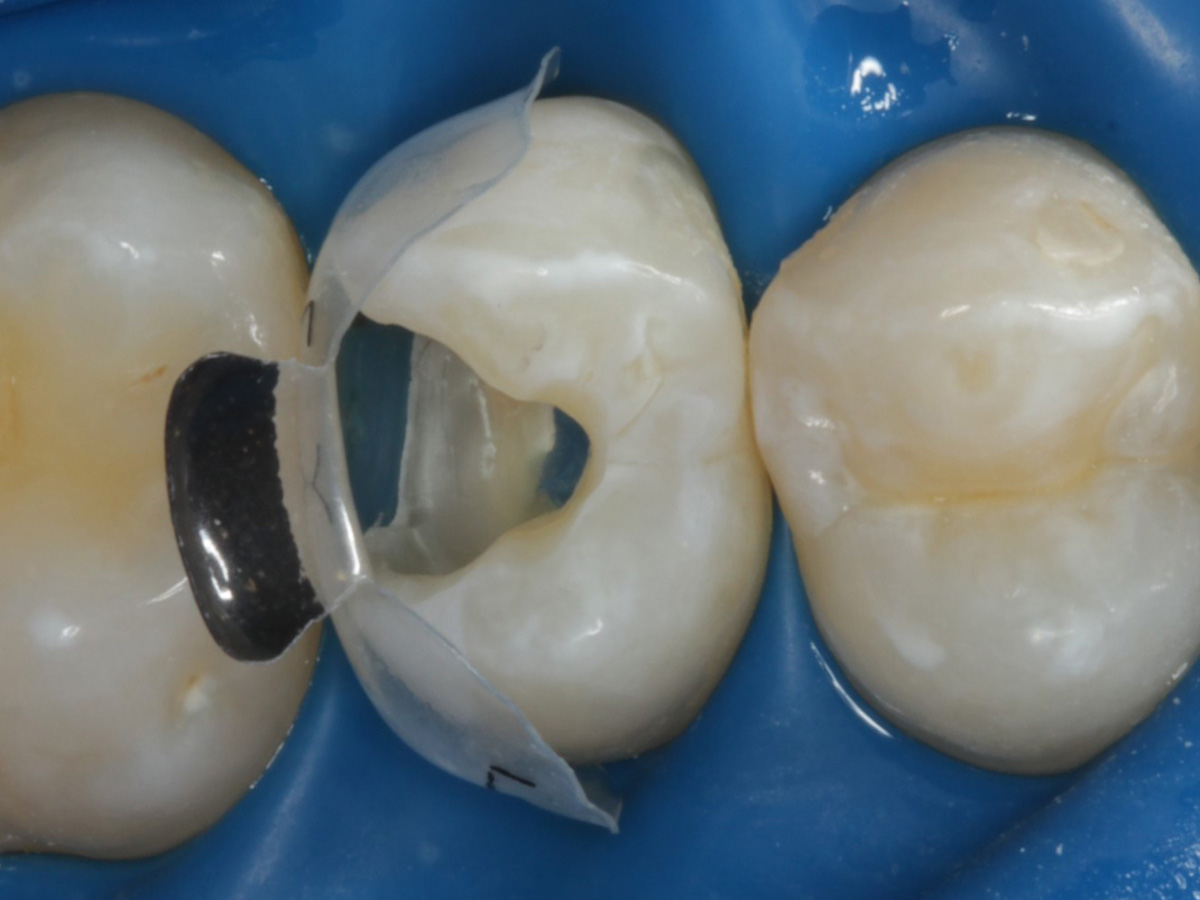

Abbildung 20

„Erste Portion“ approximal mit fließfähigem Bulkkomposit

Abbildung 21

Kavität gefüllt (Injektion Moulding: Flowkomposit, erwärmtes Seitenzahnkomposit aus Karpule)

Abbildung 22

Matrize und Twinring entfernt;  weitere Lichthärtung von bukkal und oral